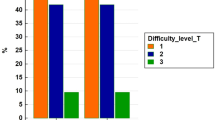

In total, 629 patients were selected from our database, including 177 patients who underwent a RLS and 452 patients who had LLS. Colorectal liver metastasis was the main indication for surgery in both groups. With the introduction of RLS, the percentage of open resections decreased significantly (32.6% from 2011 to 2020 vs. 11.5% from 2020 onward, P < 0.001). In the robotic group, redo liver surgery was more frequent (24.3% vs. 16.8%, P = 0.031) and the Southampton difficulty score was higher (4 [IQR 4 to 7] vs. 4 [IQR 3 to 6], P = 0.02). Median blood loss was lower (30 vs. 100 ml, P < 0.001), and postoperative length of stay (LOS) was shorter in the robotic group (median 3 vs. 4 days, P < 0.001). There was no significant difference in postoperative complications. Cost related to the used instruments and LOS was significantly lower in the RLS group (median €1483 vs. €1796, P < 0.001 and €1218 vs. €1624, P < 0.001, respectively), while cost related to operative time was higher (median €2755 vs. €2470, P < 0.001).

Baseline and operative characteristics

Baseline characteristics were well distributed between both groups (Table 1). Colorectal liver metastasis was the most common indication for the procedure in both groups. Benign lesions accounted for 11.8% of indications in the robotic group and 11.3% in the laparoscopic group (P = 0.84). The amount of minor and major resections was comparable. The classification of procedures according to the Brisbane classification is reported in Table 2. The number of patients who underwent redo liver surgery was higher in the robotic group (24.3% vs. 16.8%, P = 0.031), and the Southampton difficulty score[16] was also higher for robotic resections (4 [IQR 4 to 7] vs. 4 [IQR 3 to 6], P = 0.02). The robotic group included 9 patients undergoing a combined liver and bile duct resection with biliary reconstruction.